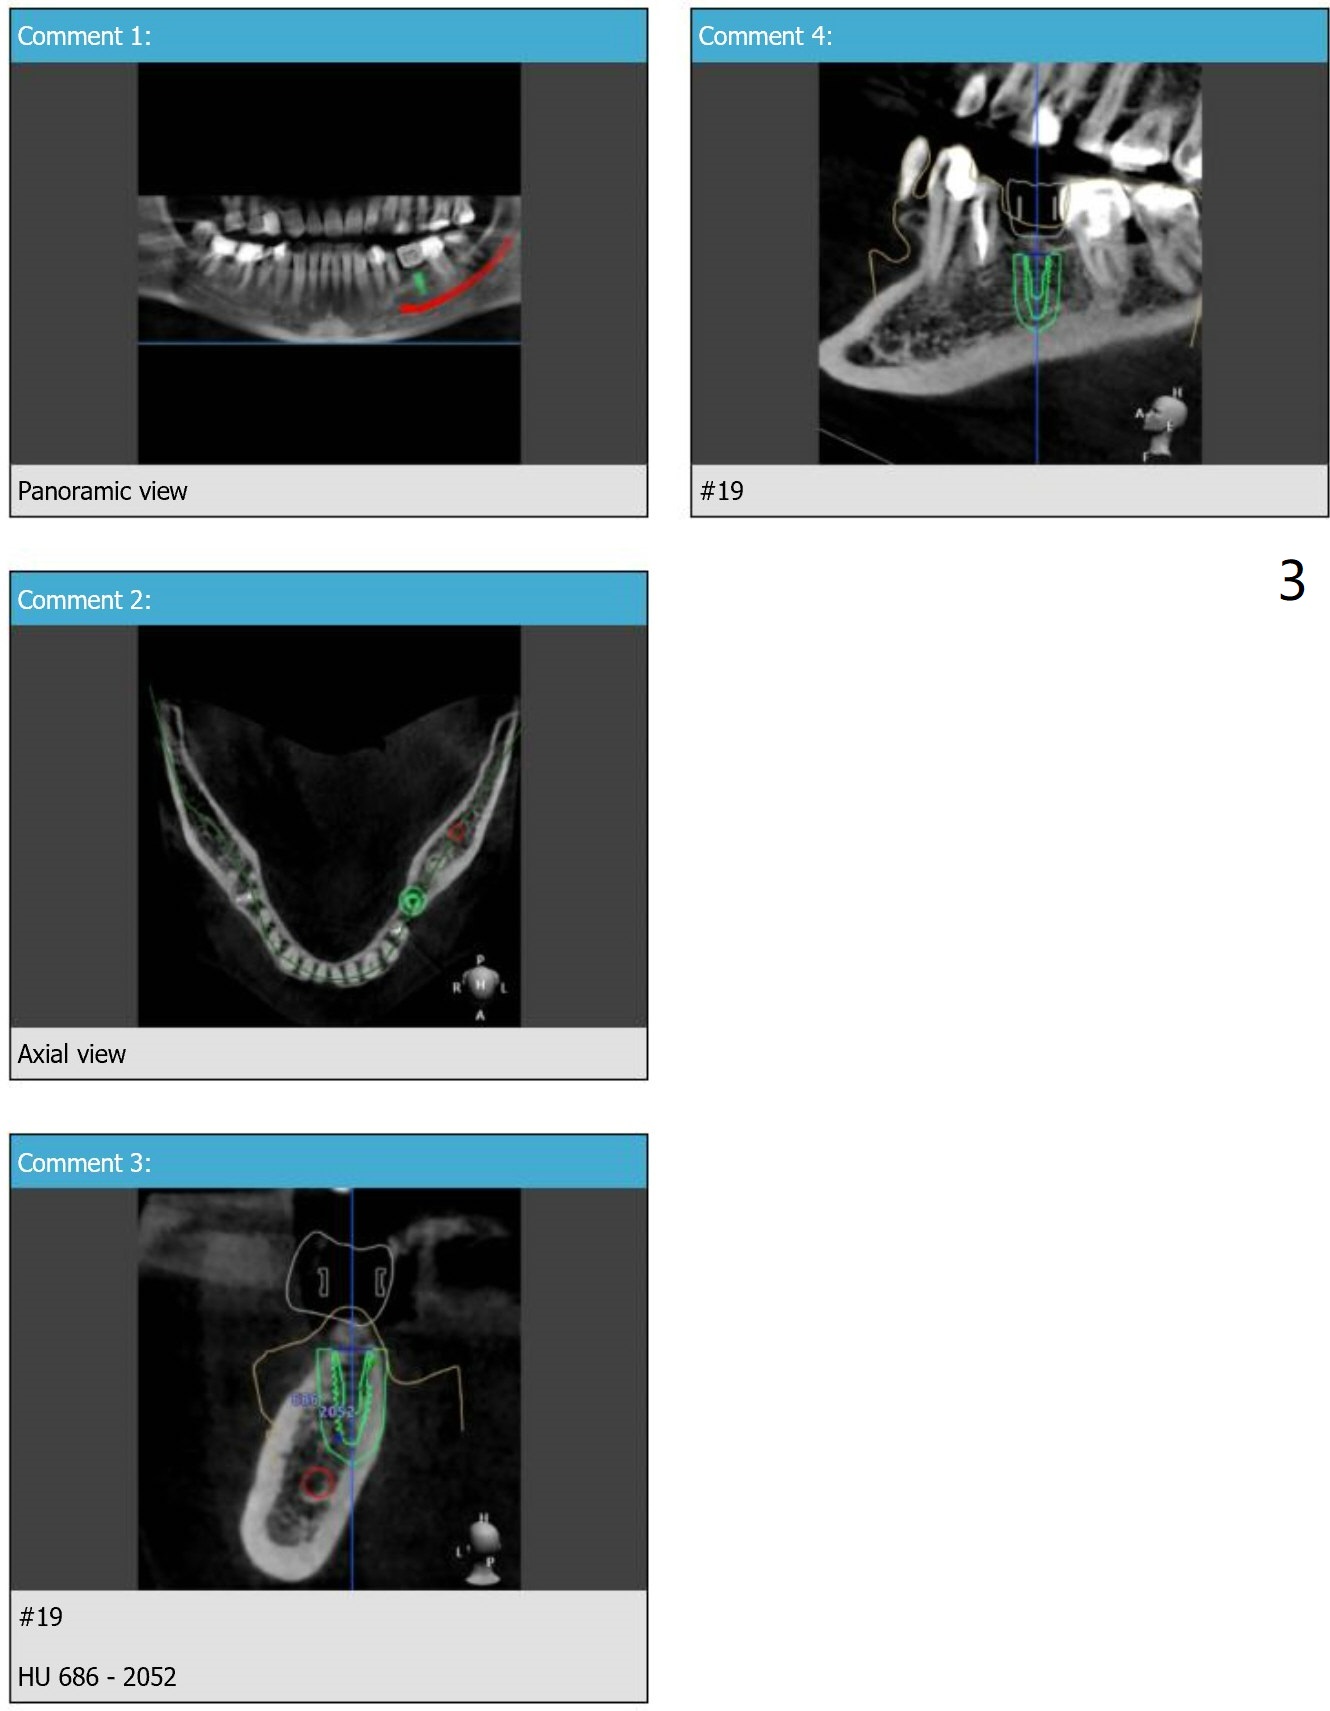

4 mm Implant for Molar

Return to Lower Molar Immediate Implant, Trajectory